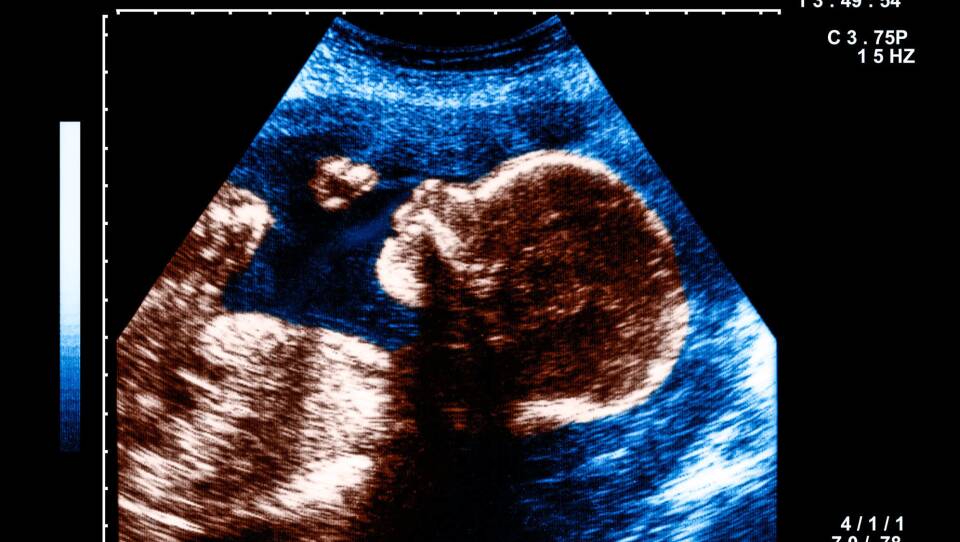

Reid and his colleagues shined the patterns at the abdomens of 39 women in their third trimester of pregnancy and used sophisticated ultrasound technology to watch in real time how the fetuses reacted.

"You can actually see the face of the fetus. And then you can actually see them move their face," Reid says. "They would move their heads more to try to track the stimuli when we showed the stimuli in an upright orientation."